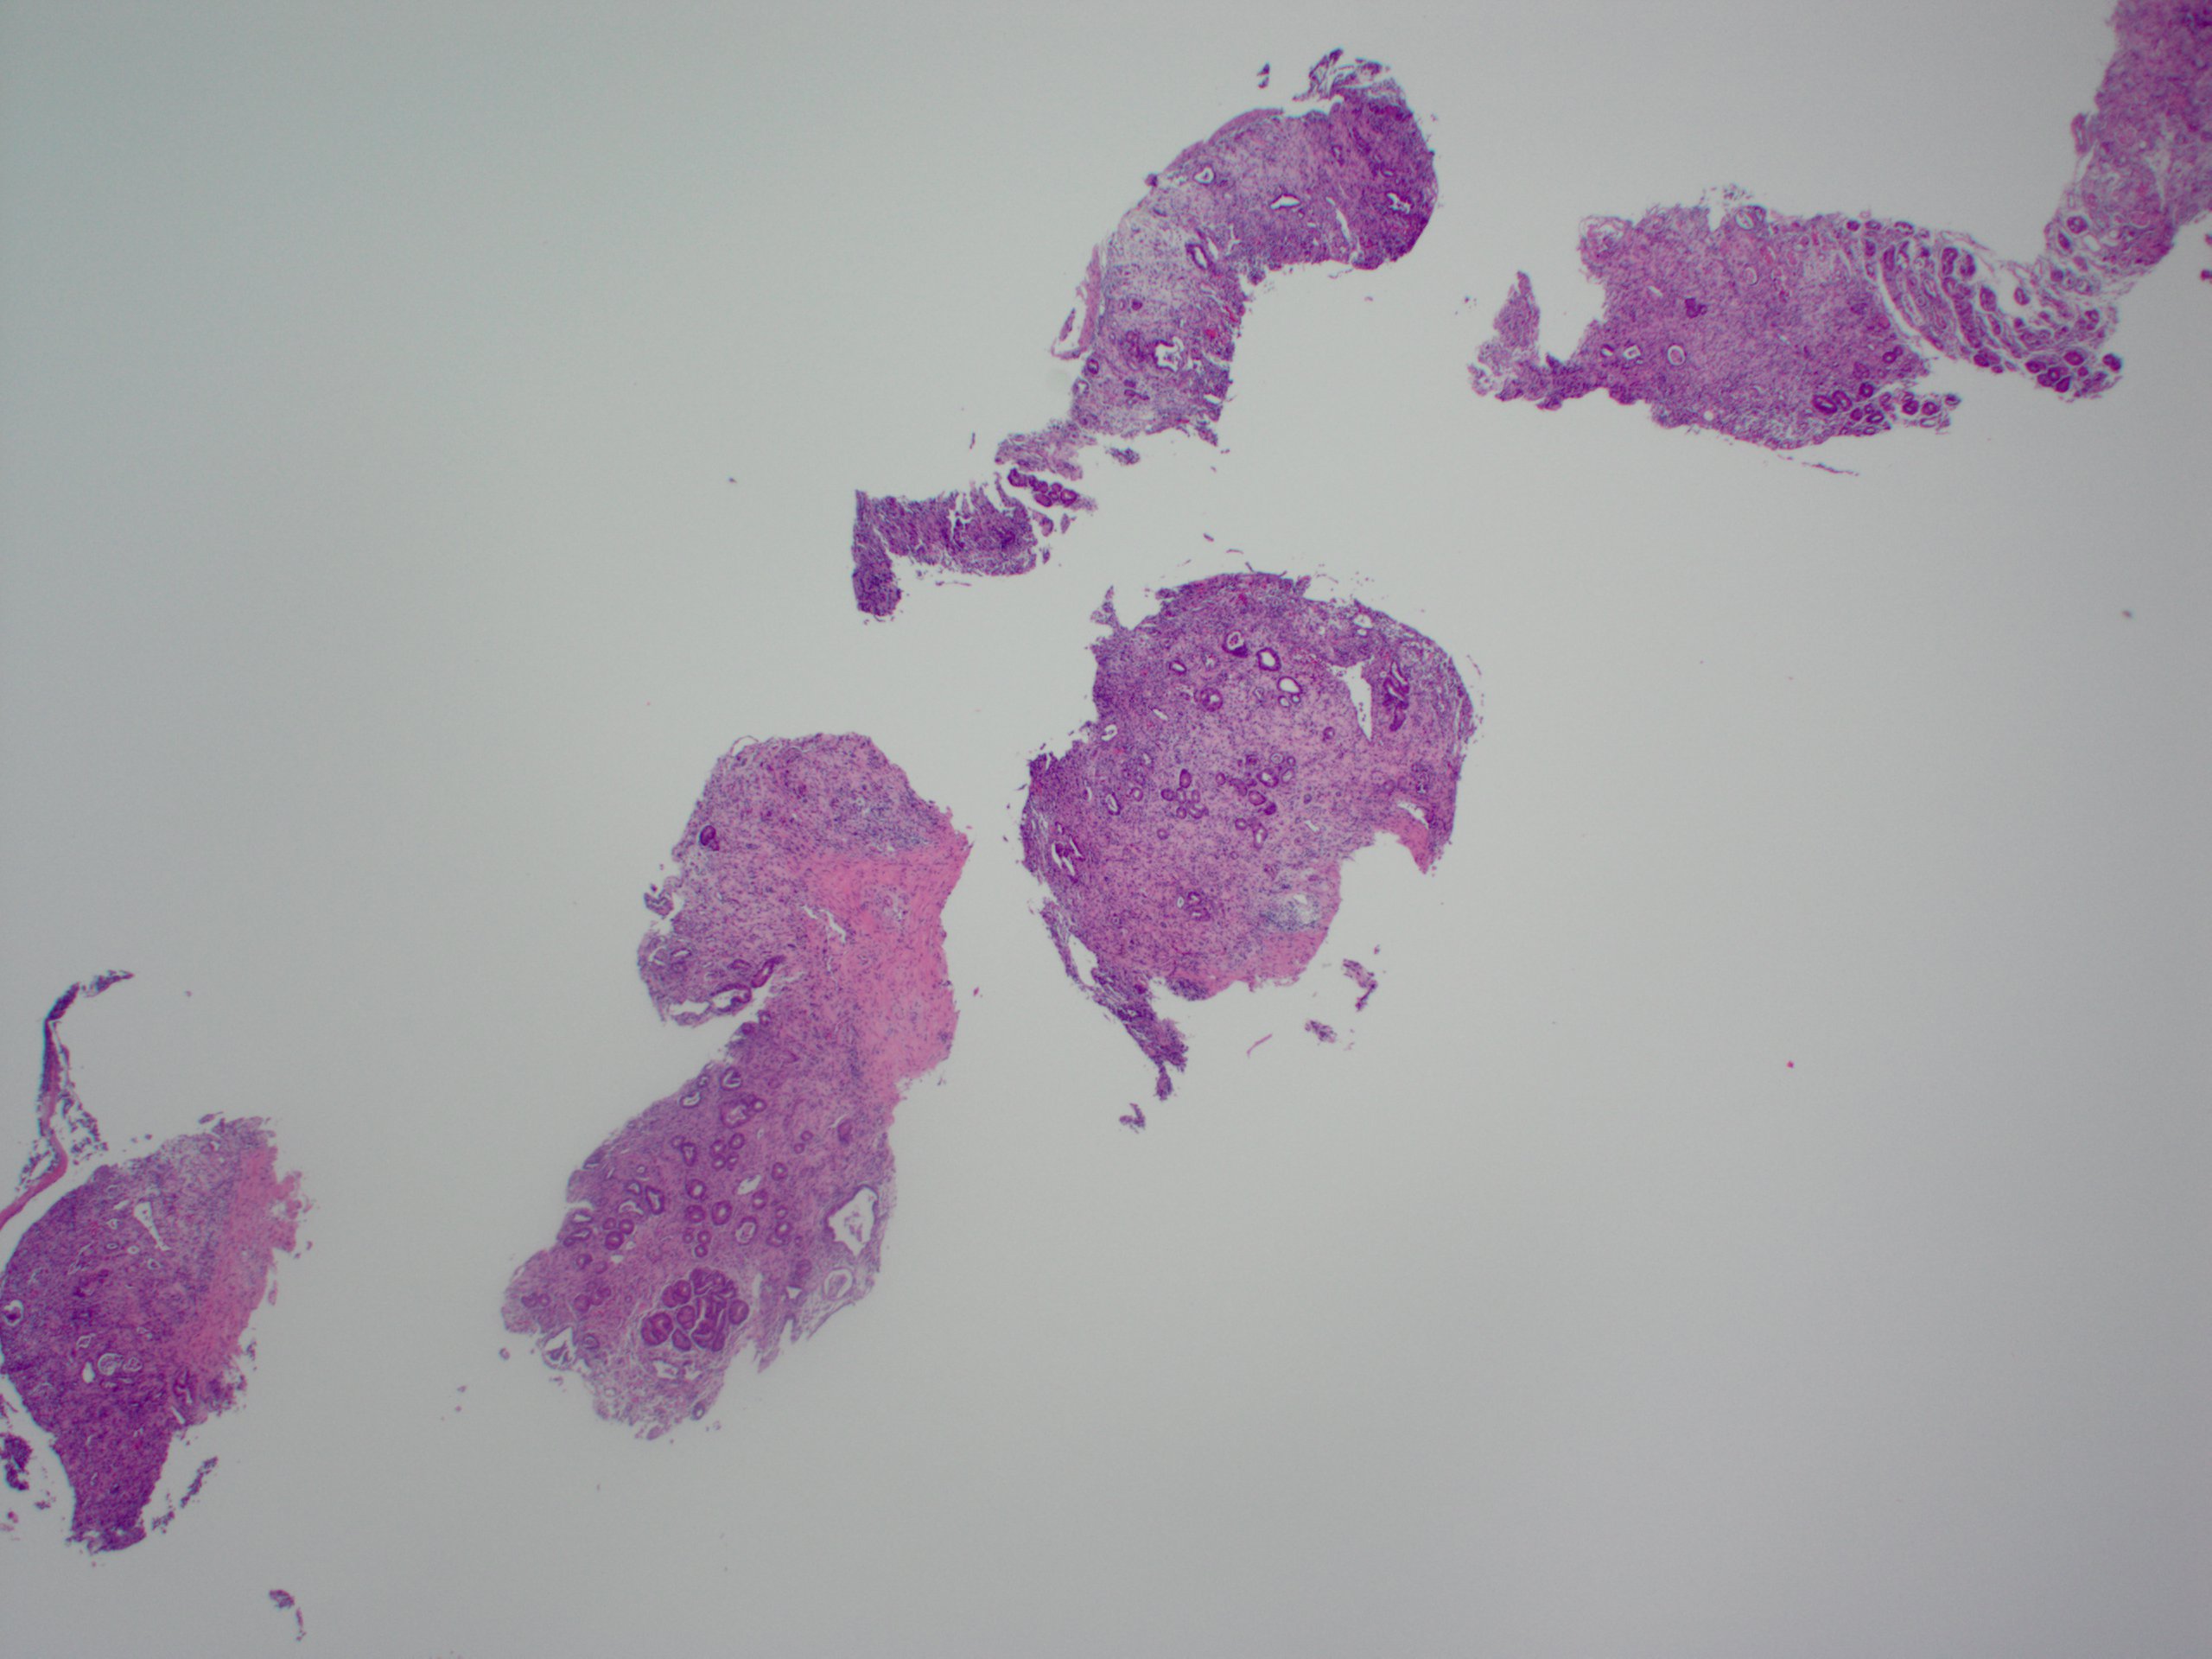

That covers the basics! Here is a direct side-by-side before and after editing in GIMP:

That covers the basics! Here is a direct side-by-side before and after editing in GIMP: